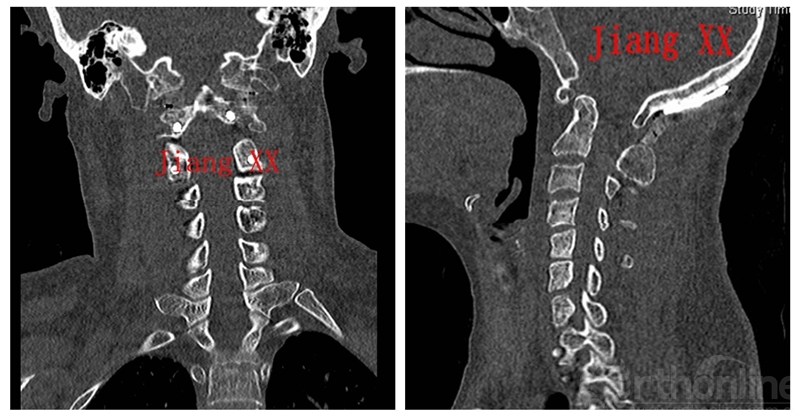

病例一:患者女性,49岁,因颈部活动受限4月入院,诊断为寰枢椎脱位,颅底凹陷。

术后CT

术后一年CT